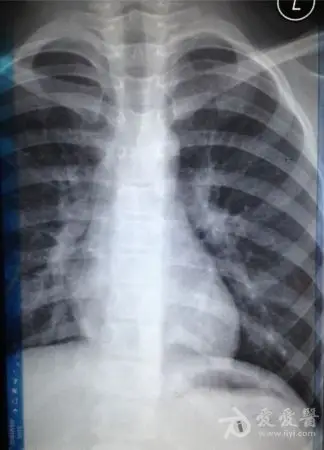

儿童肺炎时胸片怎么看呢

图片尺寸692x691

小孩得了肺炎,我们在日常中该如何护理呢? 正常胸片

图片尺寸1080x455